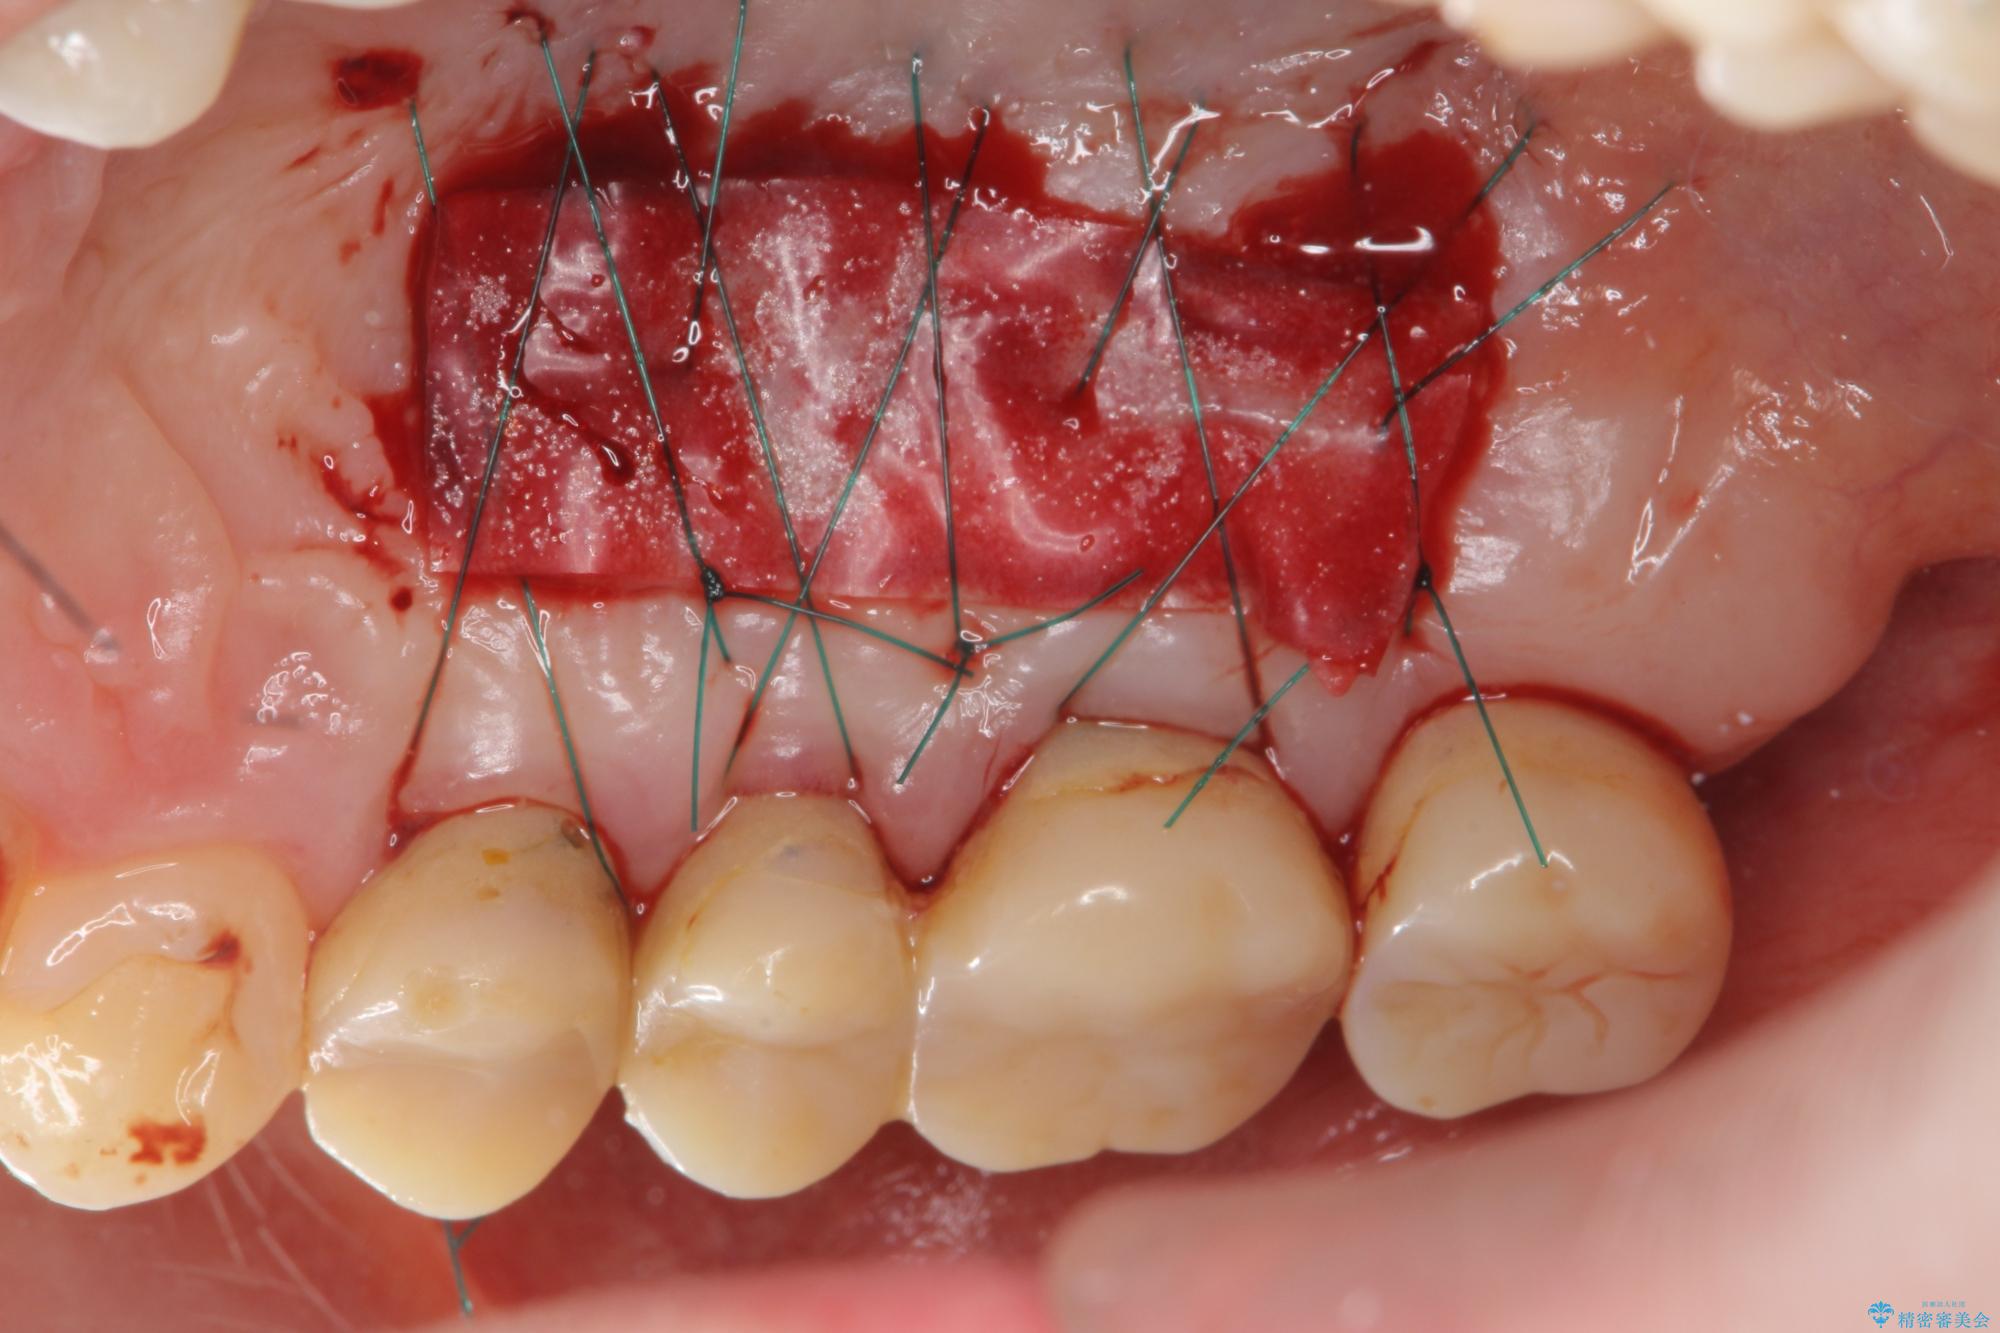

また、機能後のインプラント周囲の清掃性を高めるため遊離歯肉移植術を行っています。

インプラント周囲に強固な歯ぐきを移植することで、歯ブラシがしやすくなりインプラント周囲炎対策となります。

遊離歯肉移植術を伴うインプラント治療 治療中画像 遊離歯肉移植術を伴うインプラント治療 治療中画像 遊離歯肉移植術を伴うインプラント治療 治療中画像 遊離歯肉移植術を伴うインプラント治療 治療中画像 遊離歯肉移植術を伴うインプラント治療 治療中画像 遊離歯肉移植術を伴うインプラント治療 治療中画像